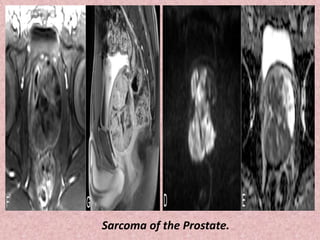

Sarcoma of the Prostate.

Prostatic sarcoma isan uncommon and heterogenous group of tumour arising from mesenchymal cells in and around the prostate. In children the most common tumour type is a prostatic rhabdomyosarcoma, which accounts for approximately a third of all prostatic sarcomas . In adults leiomyosarcomas are most common, accounting for approximately a quarter of all cases . Many other sarcomas have been reported although in general they are rare. Overall prostatic sarcomas include: rhabdomyosarcoma : most common in children leiomyosarcoma : most common in adults sarcomatoid carcinoma malignant fibrous histiocytoma phyllodes tumour (also known as cystosarcoma phyllodes of the prostate) undifferentiated stromal sarcoma